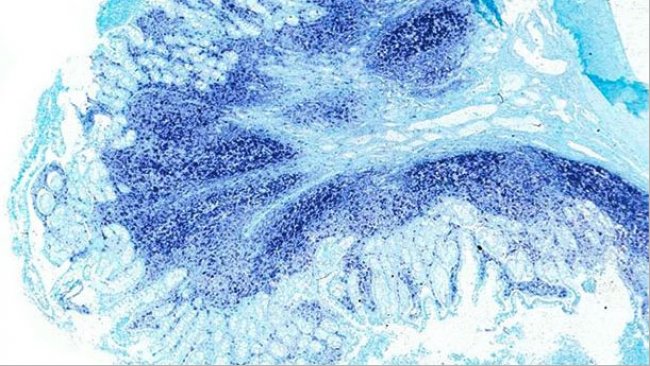

猪圆环病毒2型(PCV2)已经成为对生猪生产破坏性最大的病毒,造成相当大的经济影响(直接损失和控制疾病的花费)。PCV2是断奶仔猪多系统衰竭综合征(PMWS)的病原体,目前被称为PCV2-系统性疾病(PCV2-SD, 图 1)。流行病学和和实验研究已证明基因多样性可能影响PVC2的毒力,表现为在全球范围内出现新的基因型以及重组株的流行。也许这正是为什么PCV2种间分类颇具争议的原因。2008年,欧盟猪圆环病毒病联盟提出了以成对基因序列比较为基础的PCV2基因型标准命名法(www.pcvd.eu)。通过分析PCV2完整和衣壳(ORF2)核苷酸序列确定了2个距离阈值,分别为0.020 和0.035。当2个序列之间的遗传距离大于这两个阈值时,认为这些毒株属于不同的基因型。分析发现了4种基因型,分别命名为PCV2a, PCV2b, PCV2c和 PCV2d(也被称为PCV2b突变型)。